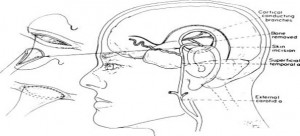

2. Інсульт. Цереброваскулярні захворювання 12%

Причини: Гіпертонія, Скорочення стовбурових клітин, вкорочення теломер